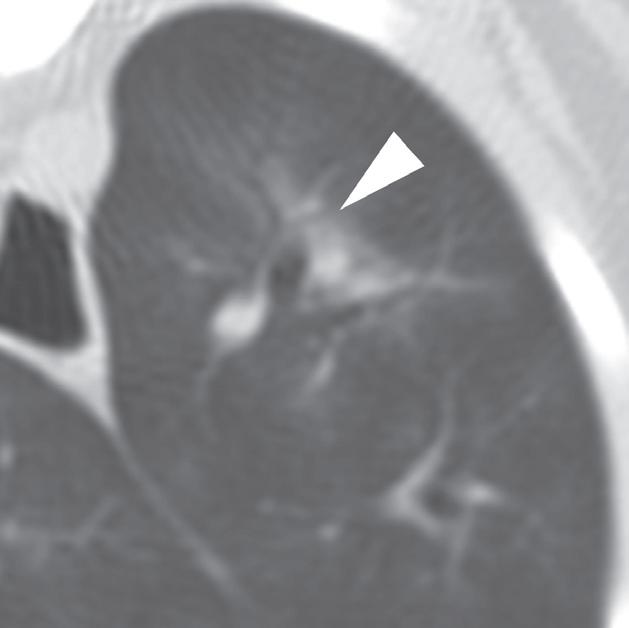

U 6-letniego samca rasy rhodesian ridgeback od 4 dni obserwowano objawy wskazujące na chorobę móżdżku. Stwierdzono słabo odgraniczony, izointensywny w T1 i hiperintensywny w T2 obszar w robaku i lewej półkuli móżdżku (a, b – groty strzałek), któremu nie towarzyszył żaden znaczący efekt masy. Po podaniu kontrastu nie zobrazowano wzmocnienia zmiany. Test immunofluorescencji pośredniej (IFA) wykazał miano zgodne z aktywnym zakażeniem Neospora. Badanie pośmiertne wykonane ok. 3 miesięcy po wstępnym rozpoznaniu potwierdziło martwicze, ziarniniakowe zapalenie móżdżku z pierwotniakami odpowiadającymi Neospora wewnątrz ognisk